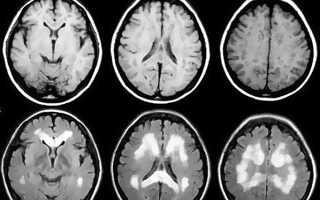

В этом случае врач обычно назначает следующие обследования:

- Ультразвуковое исследование.

- Лабораторную диагностику.

- Магнитно-резонансную томографию.

- Измерение перемещения крови внутри мозга.

Если больной жалуется на головную боль при кашле, то первое обследование, которое стоит пройти, – это МРТ головы, в результате которого будет назначено необходимое лечение.